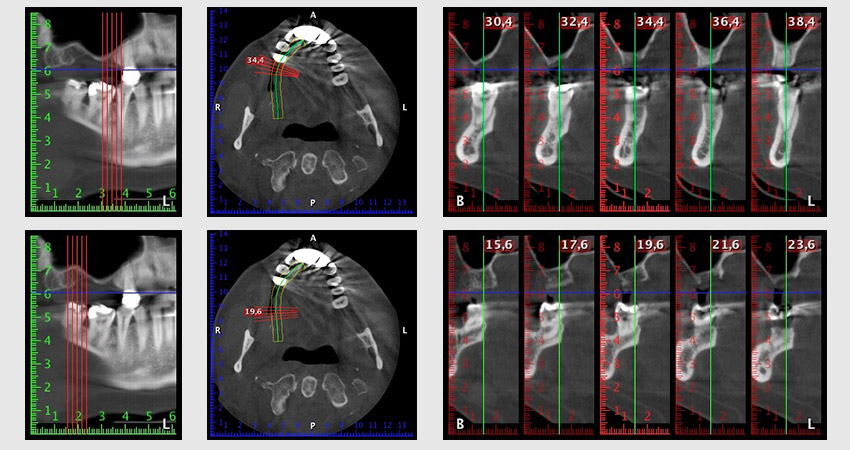

The 59-year-old patient presented with an advanced case of periodontitis, describing an unpleasant feeling and poor taste from the first quadrant in a distal direction. The clinical examination revealed generally enlarged periodontal pockets and very advanced bone atrophy in regions 16 and 14. The radiology confirmed the findings (Fig. 1). Teeth 16 and 14 could not be retained.

Image 1: Orthopantomogram with bone atrophy in region 16–14. *